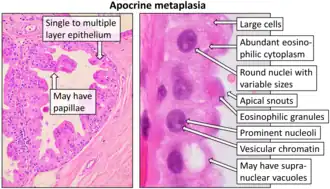

An oncocyte is an epithelial cell characterized by an excessive number of mitochondria, resulting in an abundant acidophilic, granular cytoplasm. Oncocytes can be benign or malignant.

- Apocrine-type metaplasia (breast gland only).

- Chan MKM, McGuire LJ: Cytodiagnosis of Lesions Presenting as Salivary Gland Swellings: A Report of Seven Cases. Diagn Cytopathol 8: 439-443, 1992b. - ^ Image by Mikael Häggström, MD. Reference for findings: Carlos C. Diez Freire, M.D., Shahla Masood, M.D. "Apocrine metaplasia". Pathology Outlines.

{{cite web}}: CS1 maint: multiple names: authors list (link) Last author update: 28 May 2020.